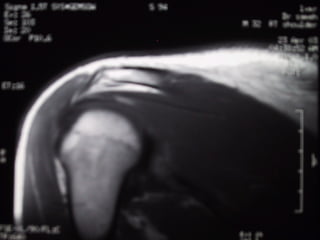

Case 6   Supraspinatus full thickness tear